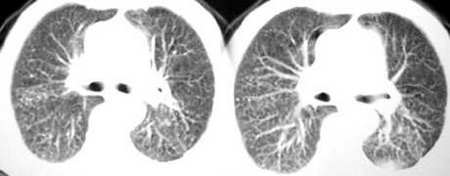

以下是引用sdqzwyx在2005-11-7 19:59:00的发言:[br]双肺弥漫大小不等的粟粒状结节影;肺纹理走行失去自然,粗细不均,边缘不规则,小叶间隔增厚;左上肺示不规则形致密影,从斑块边缘向周围伸出长短不一的致密索条影,临近的血管、支气管和叶间胸膜等结构受牵拉移位;左下肺示不规则团块状影,其内示空洞,洞内壁尚光整,左侧胸腔积液。右肺下叶背段亦示部分病灶融合。双肺可见局限性肺气肿。[br]诊断:结合病史符合三期矽肺表现(少数矽肺纤维斑块内可以形成空洞,一般认为是斑块中央感染引起坏死所致)但尘肺病人易合并肺结核,诊断可为三期+tb。所以此病人应进一步检查是否合并结核。